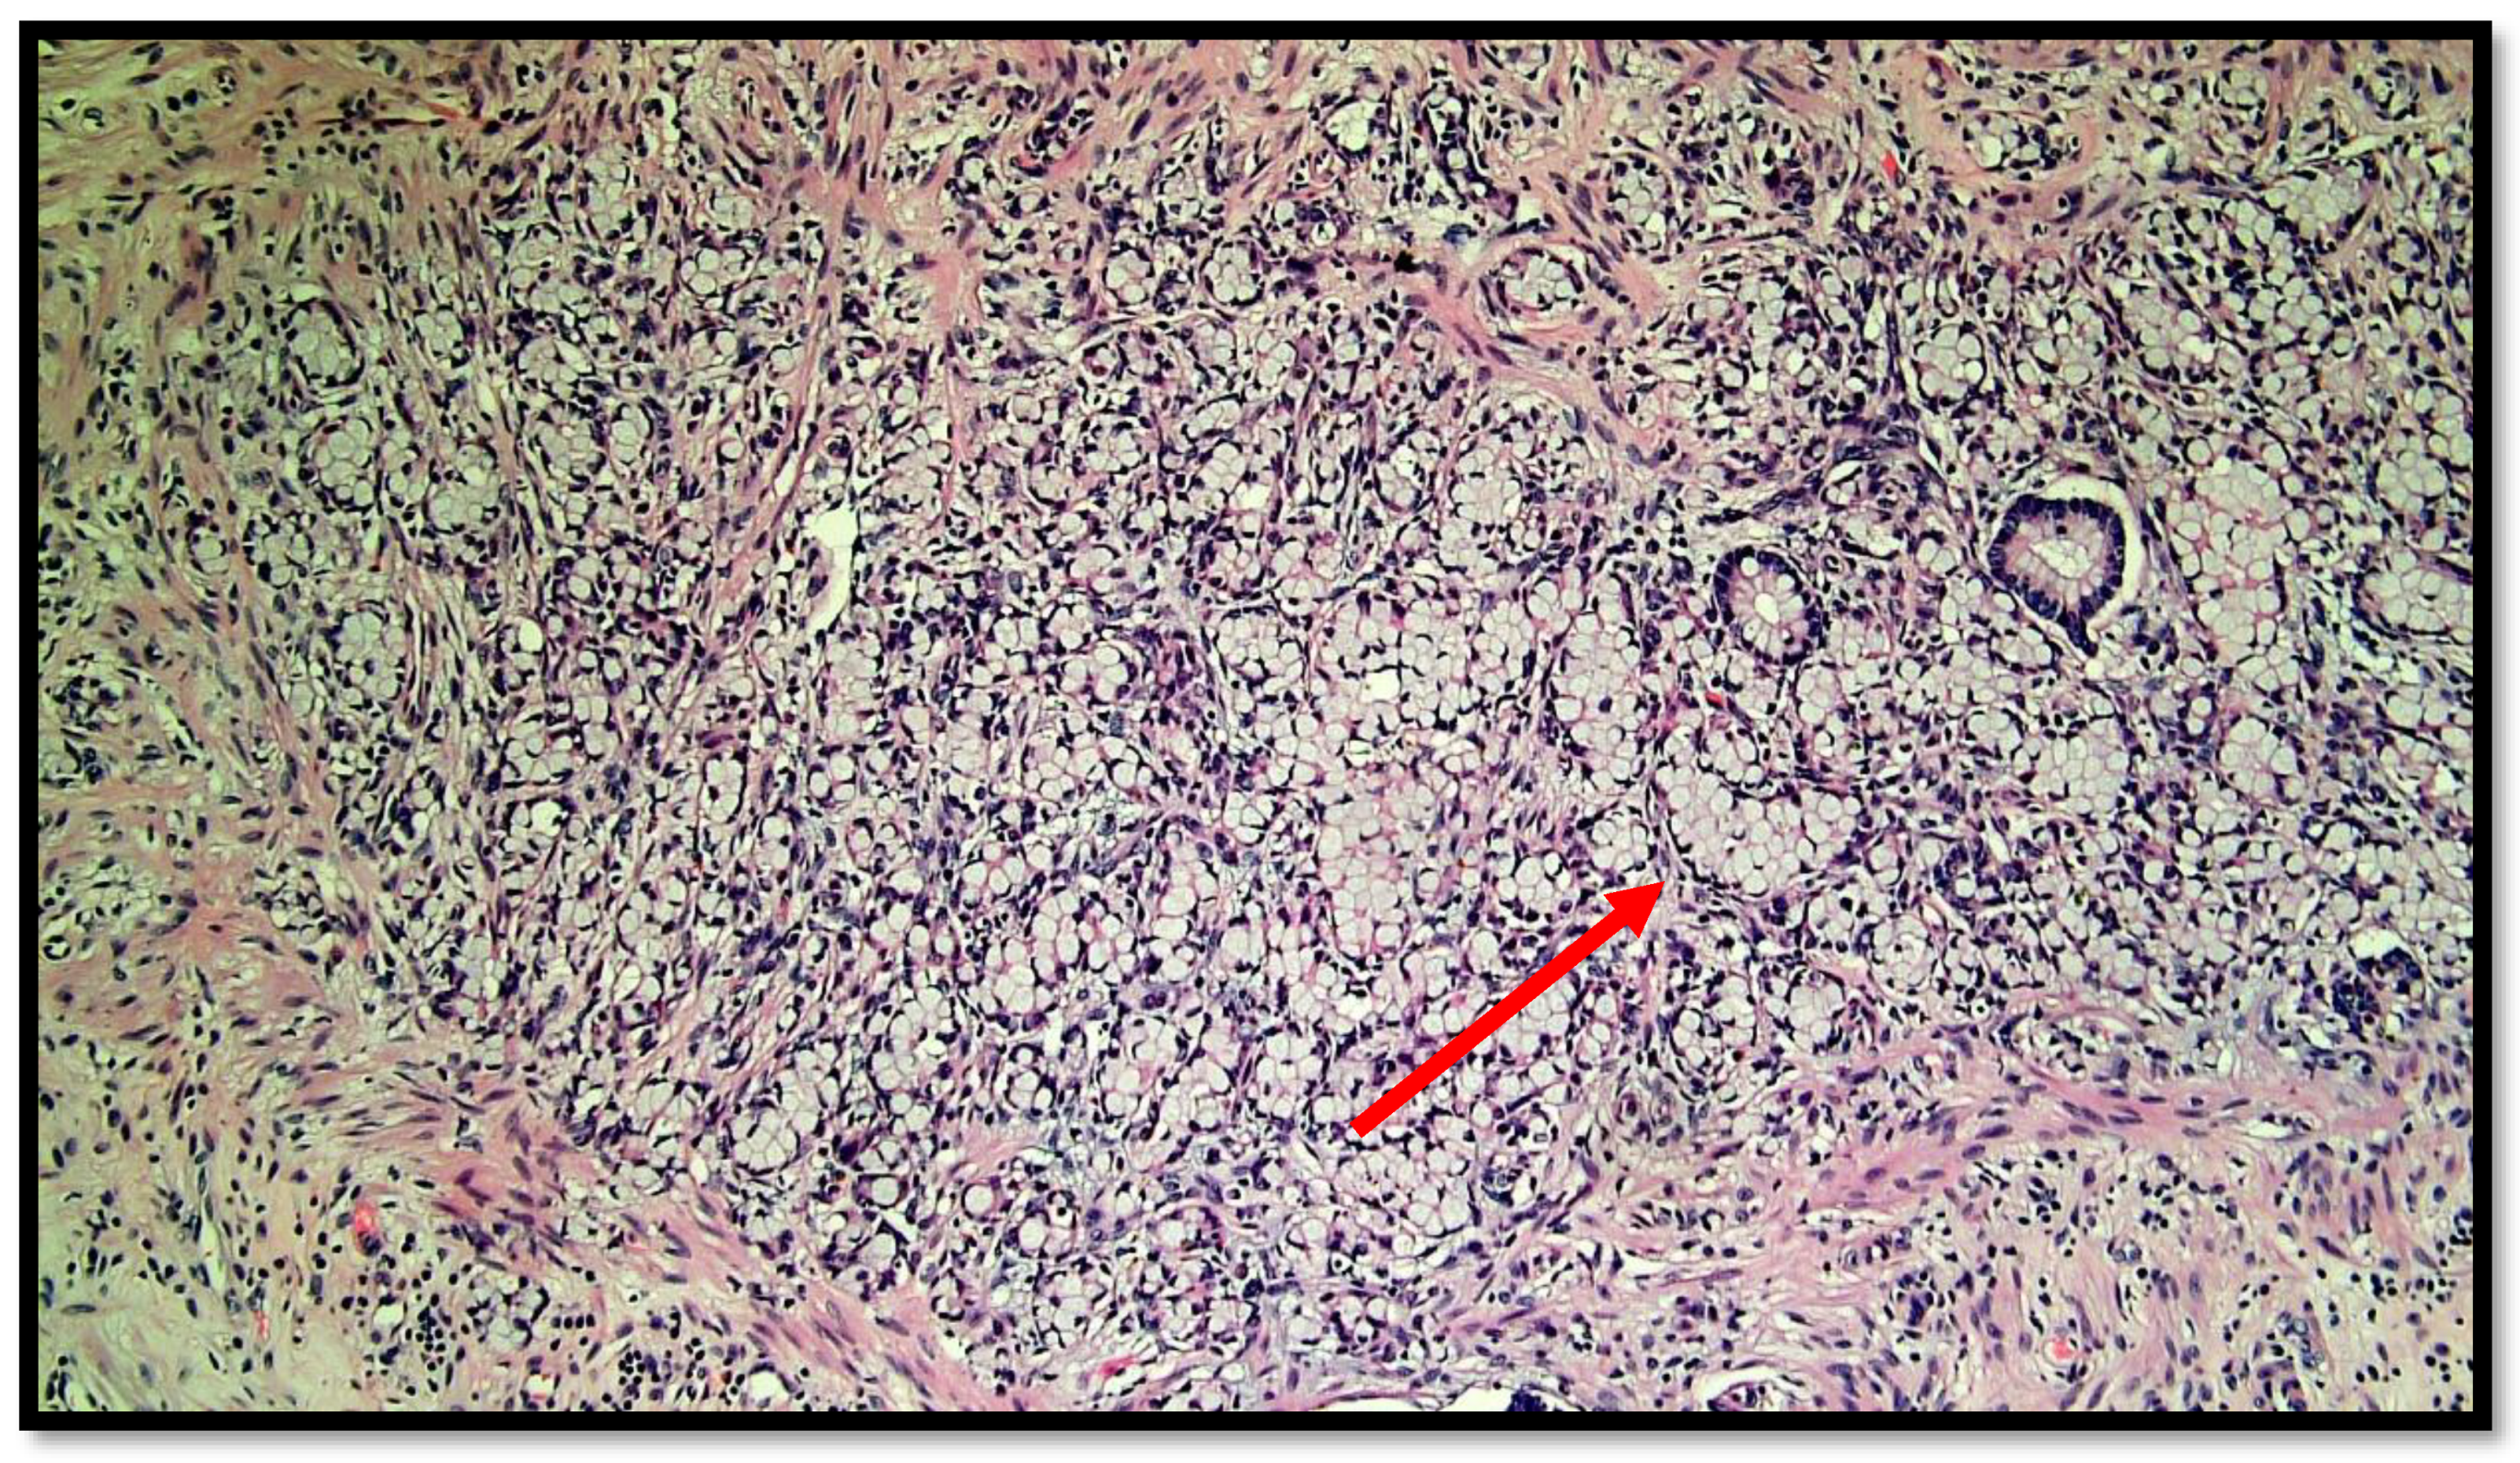

Figure 3.

Another photomicrograph showing goblet cell carcinoid and some glands in the muscular wall of the appendix. (Hematoxylin–eosin, original magnification 20×).